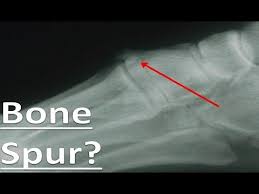

Most patients with mild or moderate nerve compression and irritation from bone spurs can manage their symptoms effectively without surgery. Common locations for bone spurs are in the back, or sole, of the heel bone of the foot, around joints that have degenerated cartilage, and in the spine adjacent to. Grasp the toes of your painful foot and slowly pull them toward you in a controlled fashion. Natural treatment tips for bone spurs on top of the foot. Bone spurs are hard bumps that form around your joints or on your spine.

Presuming it is one of those two conditions, there are treatments readily available. Heel bone spurs are only treated if they are causing problems. Suggest remedies for the bone spur and make. These top of foot bone spurs occur when the foot flattens excessively and these bones are pressed together as seen in figure one and as shown. If the bone spurs affect the foot or heel, a doctor may recommend special pads or inserts for shoes called orthotics to help take the pressure off. Bone spurs are hard bumps that form around your joints or on your spine. It is comprised of the minerals that are. The everyday reality, however, is far more mundane and has much more to do with bones than chaps. Treating bone spurs on top of the foot. Sometimes, they can appear on the top of the foot and become visible through the skin. Do you have a bump, lump or bone spur on top of your foot? The #1 cause of bone spurs on top of the foot is almost always due to bone arthritis, foot flattening and ligament stretching. If there is noticeable lump, but no pain or other symptoms, they will usually be left alone.

Treatment for bone spurs depends on the symptoms one is having. What can cause a bone spur on foot? Bone spurs (osteophytes) often they might not require treatment. A bone spur on top of your foot can happen in many different areas. The #1 cause of bone spurs on top of the foot is almost always due to bone arthritis, foot flattening and ligament stretching. Bone spurs are hard bumps that form around your joints or on your spine. Presuming it is one of those two conditions, there are treatments readily available. Toe bone spurs can be painful with shoe pressure. Common locations for bone spurs are in the back, or sole, of the heel bone of the foot, around joints that have degenerated cartilage, and in the spine adjacent to. Once bone is formed it is there to stay unless you consider surgery. Nonsurgical treatment for bone spurs. Treating bone spurs on top of the foot. When they occur in the foot, they.